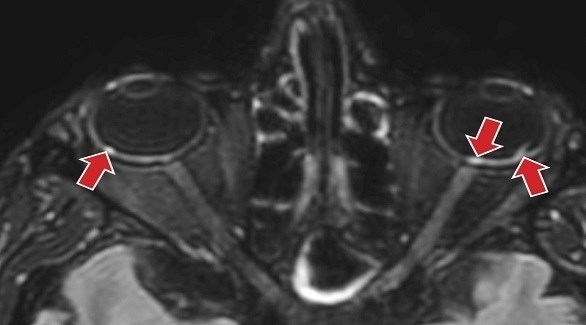

وحلل الباحثون فحوصات بالرنين المغناطيسي لـ 129 مريض عانوا من أعراض كورونا الحادة، واكتشفوا أن 9 منهم يعانون من تشوه واحد أو أكثر في الجزء الخلفي من بؤبؤ العين.

وعندما يدخل مريض بكورونا إلى المستشفىن فإنه يوضع في الغالب مستلقياً على جبهته لمساعدته على التنفس، في وضعية الانبطاح، للحصول على تدفق أقوى للأكسجين إلى الرئتين.

وقال الخبراء إن ذلك قد يكون أحد أسباب تطور العقيدات في العين لأن الأوردة فيها لا تجف، وأن كل المصابين الذين شاركوا في الدراسة كانوا مستلقين بهذه الوضعية في العناية المركزة.